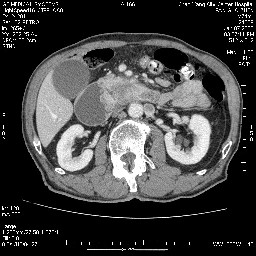

女,74岁,呕吐10余日

壶腹部的占位性病变,考虑为十二指肠癌并梗阻,但脾内多发性低密度区为转移吗?

还有胃、脾之间可见有侧支循环建立。左肾盂积水。

十二指肠水平段腔内占位伴梗阻,中等度较为均匀的强化,洗脱慢,区域淋巴结显示增多,符合腺癌表现。下腔静脉变异。

十二指肠降段扩张,水平段狭窄成鼠尾状,肠壁明显增厚,胰腺勾突增大成不均匀强化,其内可见低密度区,胆囊增大,1十二指肠水平段腺癌侵犯胰腺勾突可能大,2胰腺癌侵犯十二指肠(只有胆囊增大没有肝内外胆管扩张不好解释)代除外.

十二指肠降段扩张,水平段狭窄成鼠尾状,肠壁明显增厚,胰腺勾突增大成不均匀强化,其内可见低密度区,胆囊增大,1十二指肠水平段腺癌侵犯胰腺勾突可能大,2胰腺癌侵犯十二指肠 。

今日手术结果:胰腺钩突癌侵犯十二直肠,腹腔淋巴结转移.